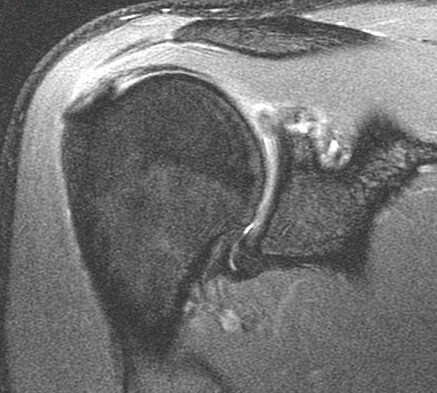

19 y/o college pitcher. Pain with throwing.

Posterior superior glenoid bone build up from chronic peel back stress. There are superimposed acute edematous changes. Abstract from Burkarts article describing it is included. Reference article.

Posterior Peel Back Lesion of Internal Impingement